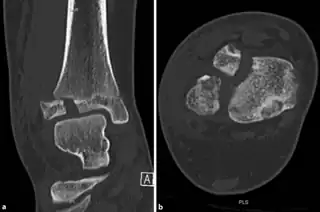

- CT scan

a,b)CT scan, coronal and axial plane of a Tillaux fracture in a male

It occurs in older children at the end of growth. Variability in fracture pattern is due to progression of physeal closure as anterolateral part of distal tibial physis is the last to close. When the lateral physis is the only portion not fused, external rotation may lead to Tillaux or Triplane fractures.[4]